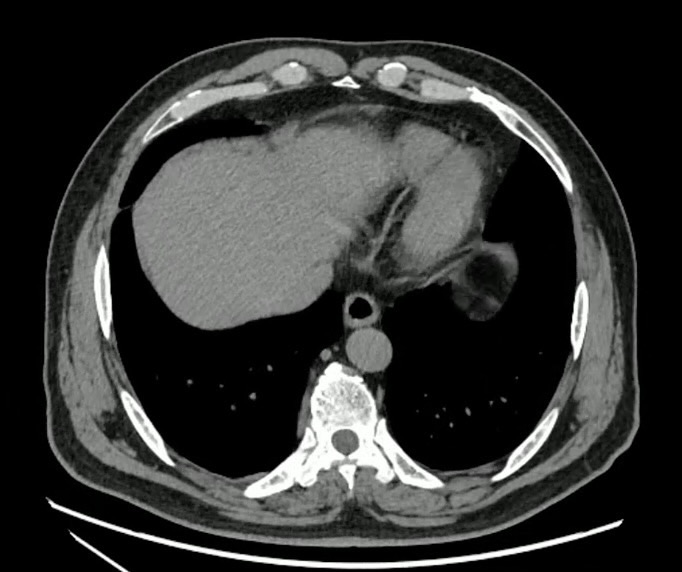

【患者信息】:男,60岁。

【主诉】:间断上腹部疼痛30天。

十二指肠溃疡 (97)